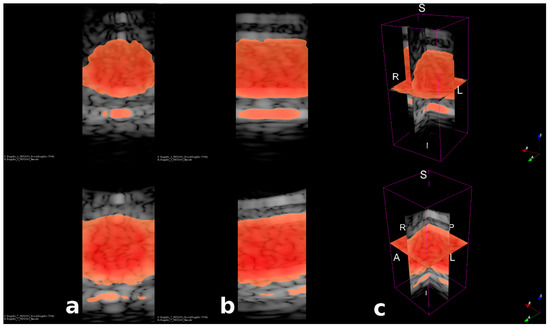

3.3. Fast Volumetric Imaging for Doppler Application